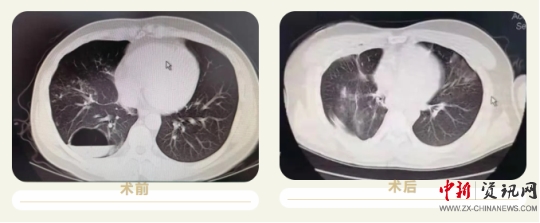

上蔡縣人民醫(yī)院成功實施首例胸腔鏡右肺下葉切除術(shù)

患者董某,男,32歲,因“咳嗽、咳痰伴咯血2天”收入院,患者及家屬敘述于本次入院兩天前受涼后出現(xiàn)咳嗽,咳白色粘液,有咯血,主要為痰中帶血,呈鮮血,量較少,活動后氣促,來上蔡縣人民醫(yī)院治療,經(jīng)ct檢查后以“肺囊腫”收住入院,患者病變位置于右肺下葉,手術(shù)切除區(qū)域毗臨心臟及胸腔大血管,同時該手術(shù)需要全麻,術(shù)中及圍手術(shù)期管理難度大,經(jīng)過上蔡縣人民醫(yī)院神經(jīng)外科團(tuán)隊及麻醉科主任陳樹軍的充分論證和術(shù)前準(zhǔn)備后決定行胸腔鏡下手術(shù)治療,手術(shù)過程順利,目前患者各項生命體征平穩(wěn),正在康復(fù)中。